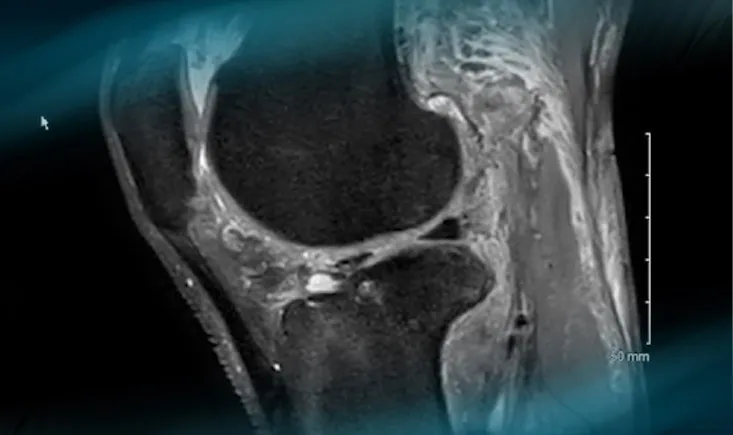

A 33-year-old male long jump parasport athlete with a transtibial amputated leg suffered an ACL rupture from k…

ACL repair is currently a hot topic in knee arthroscopy.